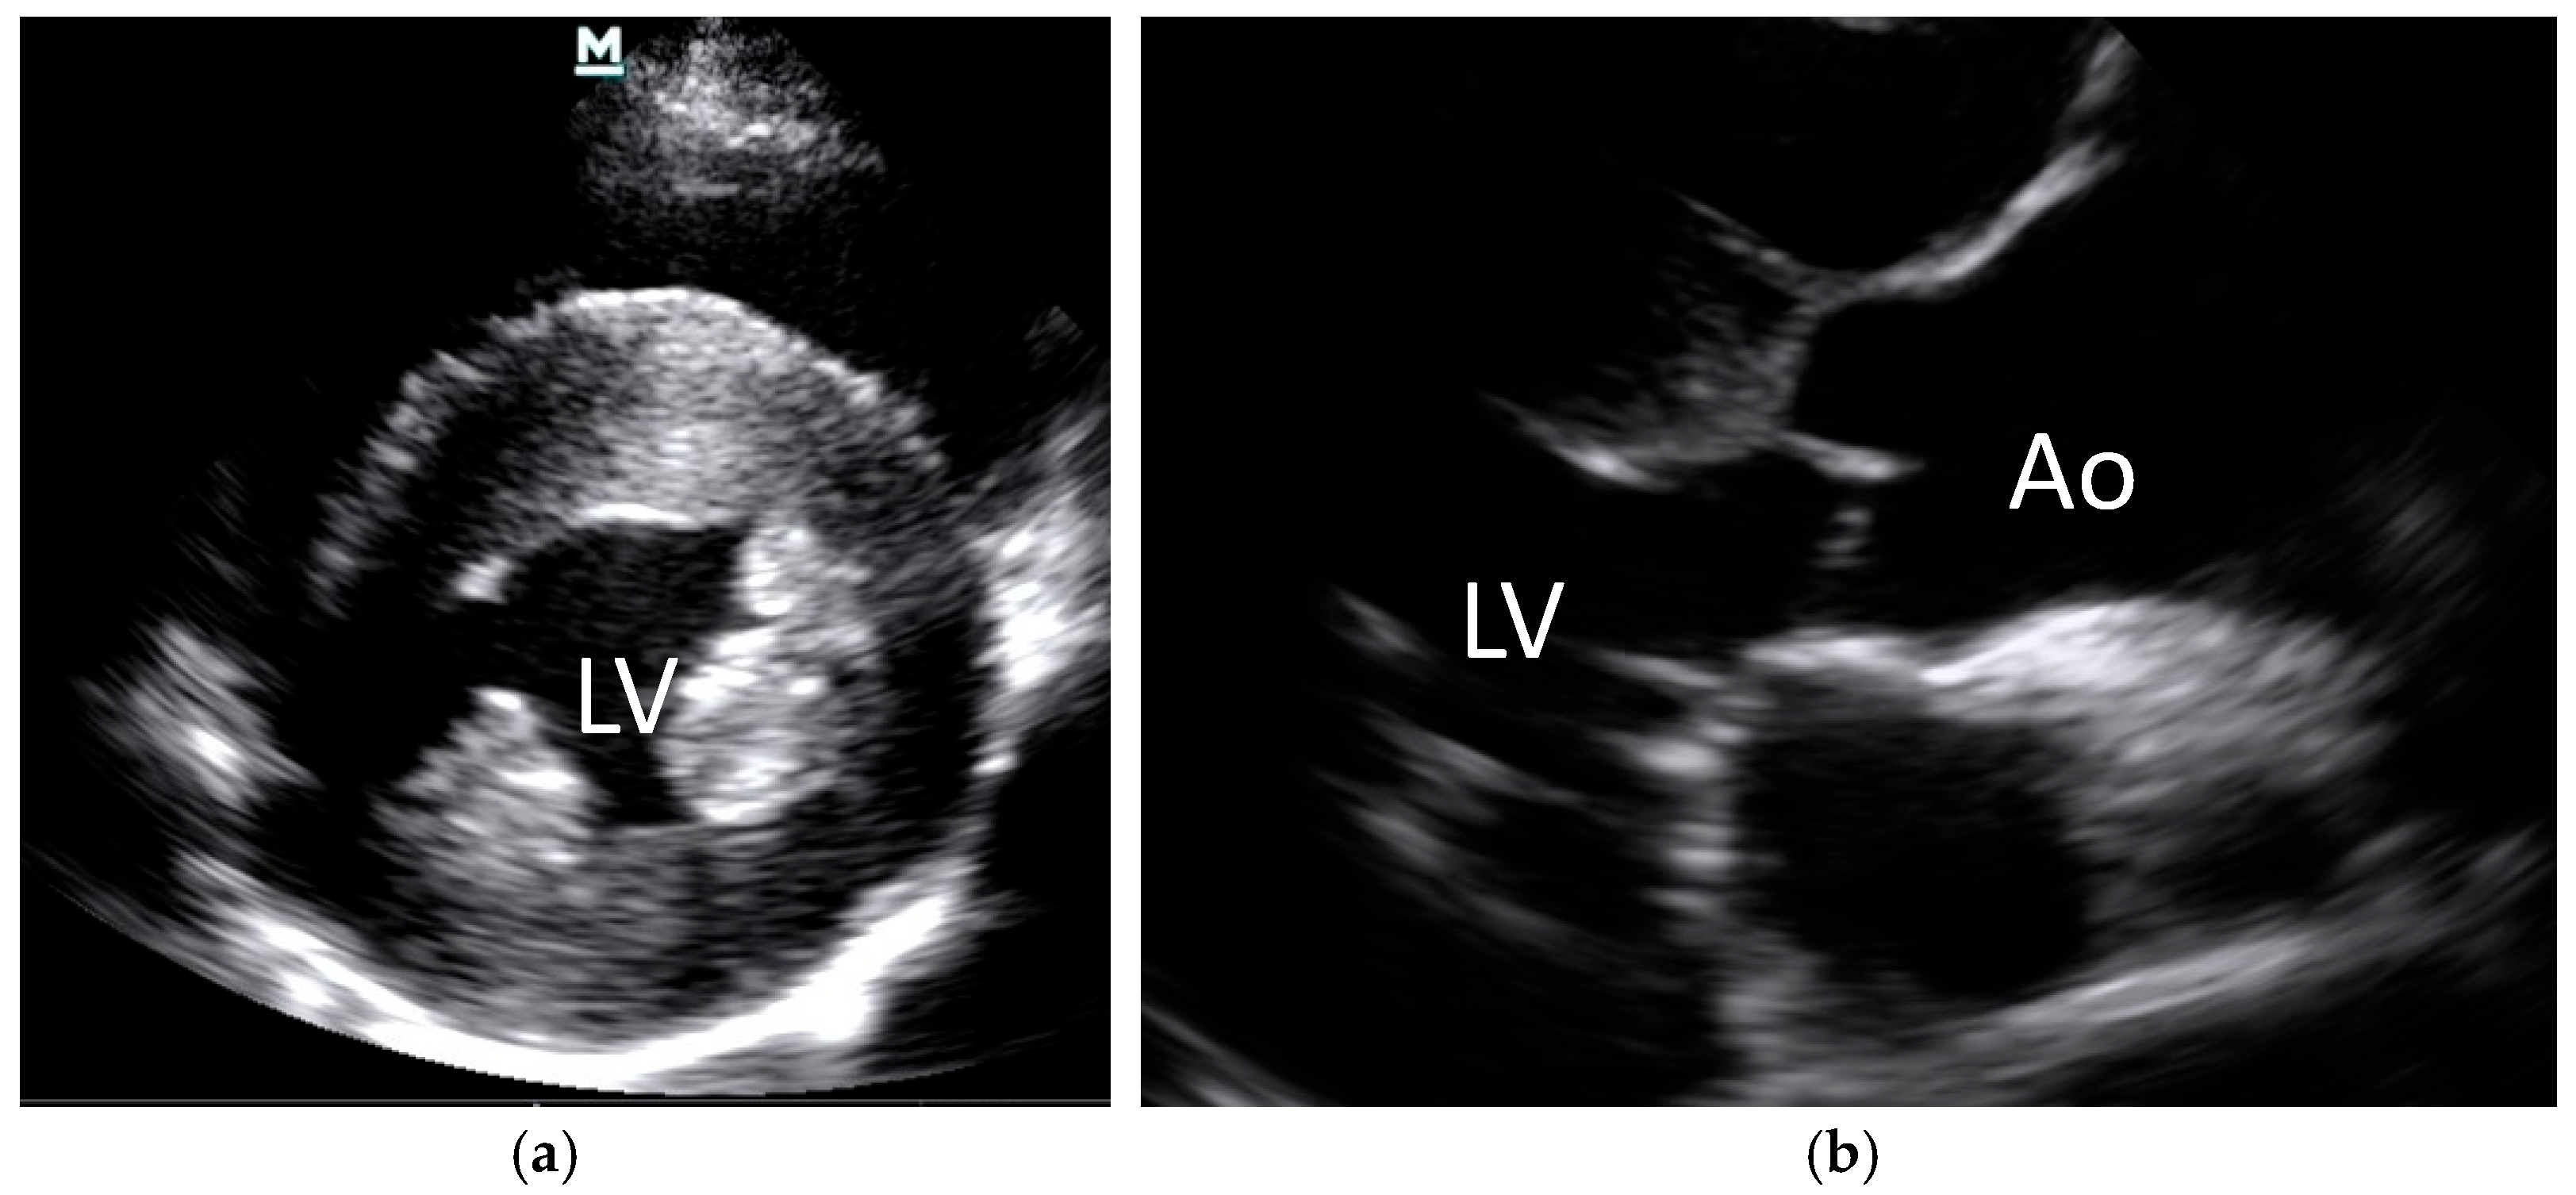

- Nelson, O.L.; Reidesel, E.; Ware, W.A.; Christensen, W.F. Echocardiographic and radiographic changes associated with systemic hypertension in cats. J. Vet. Intern. Med. 2002, 16, 418–425. [Google Scholar] [CrossRef]